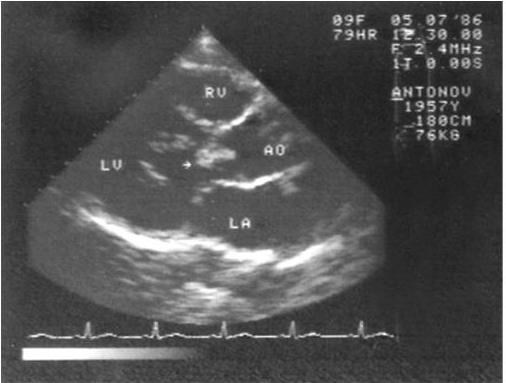

Рис. 1.7. Эхокардиограмма больного инфекционным эндокардитом. Вегетация (указана стрелкой) на аортальном клапане

Наиболее информативным инструментальным методом исследования является эхокардиография, особенно транспищеводная, выявляющая достаточно мелкие вегетации (не менее 5 мм) и сопутствующие изменения клапанного аппарата (рис. 1.7). Вегетации обычно появляются не раньше, чем через 2 недели после начала заболевания и длительно сохраняются после выздоровления (несколько месяцев). Ультразвуковое исследование, как правило, выявляет увеличение размеров селезенки.